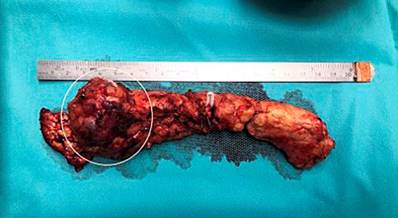

Se realizó una pancreatectomía distal por laparoscopia con preservación del bazo, en la cual se encontró un tumor en el cuello del páncreas de aproximadamente 5 cm (Figura 1) que no comprometía las estructuras vasculares y una adenopatía sobre la arteria hepática, la cual se logró resecar. El reporte histopatológico confirmó el diagnóstico de neoplasia sólida pseudopapilar (Figura 2) con adenopatía negativa para tumor. No hubo complicaciones posoperatorias. Tras 4 meses de la intervención, el estado de la paciente es adecuado, con modulación del dolor abdominal. Se le realizó una TAC de abdomen con contraste de control con hallazgos posquirúrgicos de pancreatectomía distal e infarto esplénico antiguo.

Figura 2 A. Las células tumorales muestran un citoplasma eosinófilo, algunos con vacuolas intracitoplasmáticas perinucleares y glóbulos hialinos. B. Lesión tumoral constituida por nidos sólidos de células que se agregan alrededor de los vasos sanguíneos y generan una arquitectura pseudopapilar. Fuente: archivo de los autores.